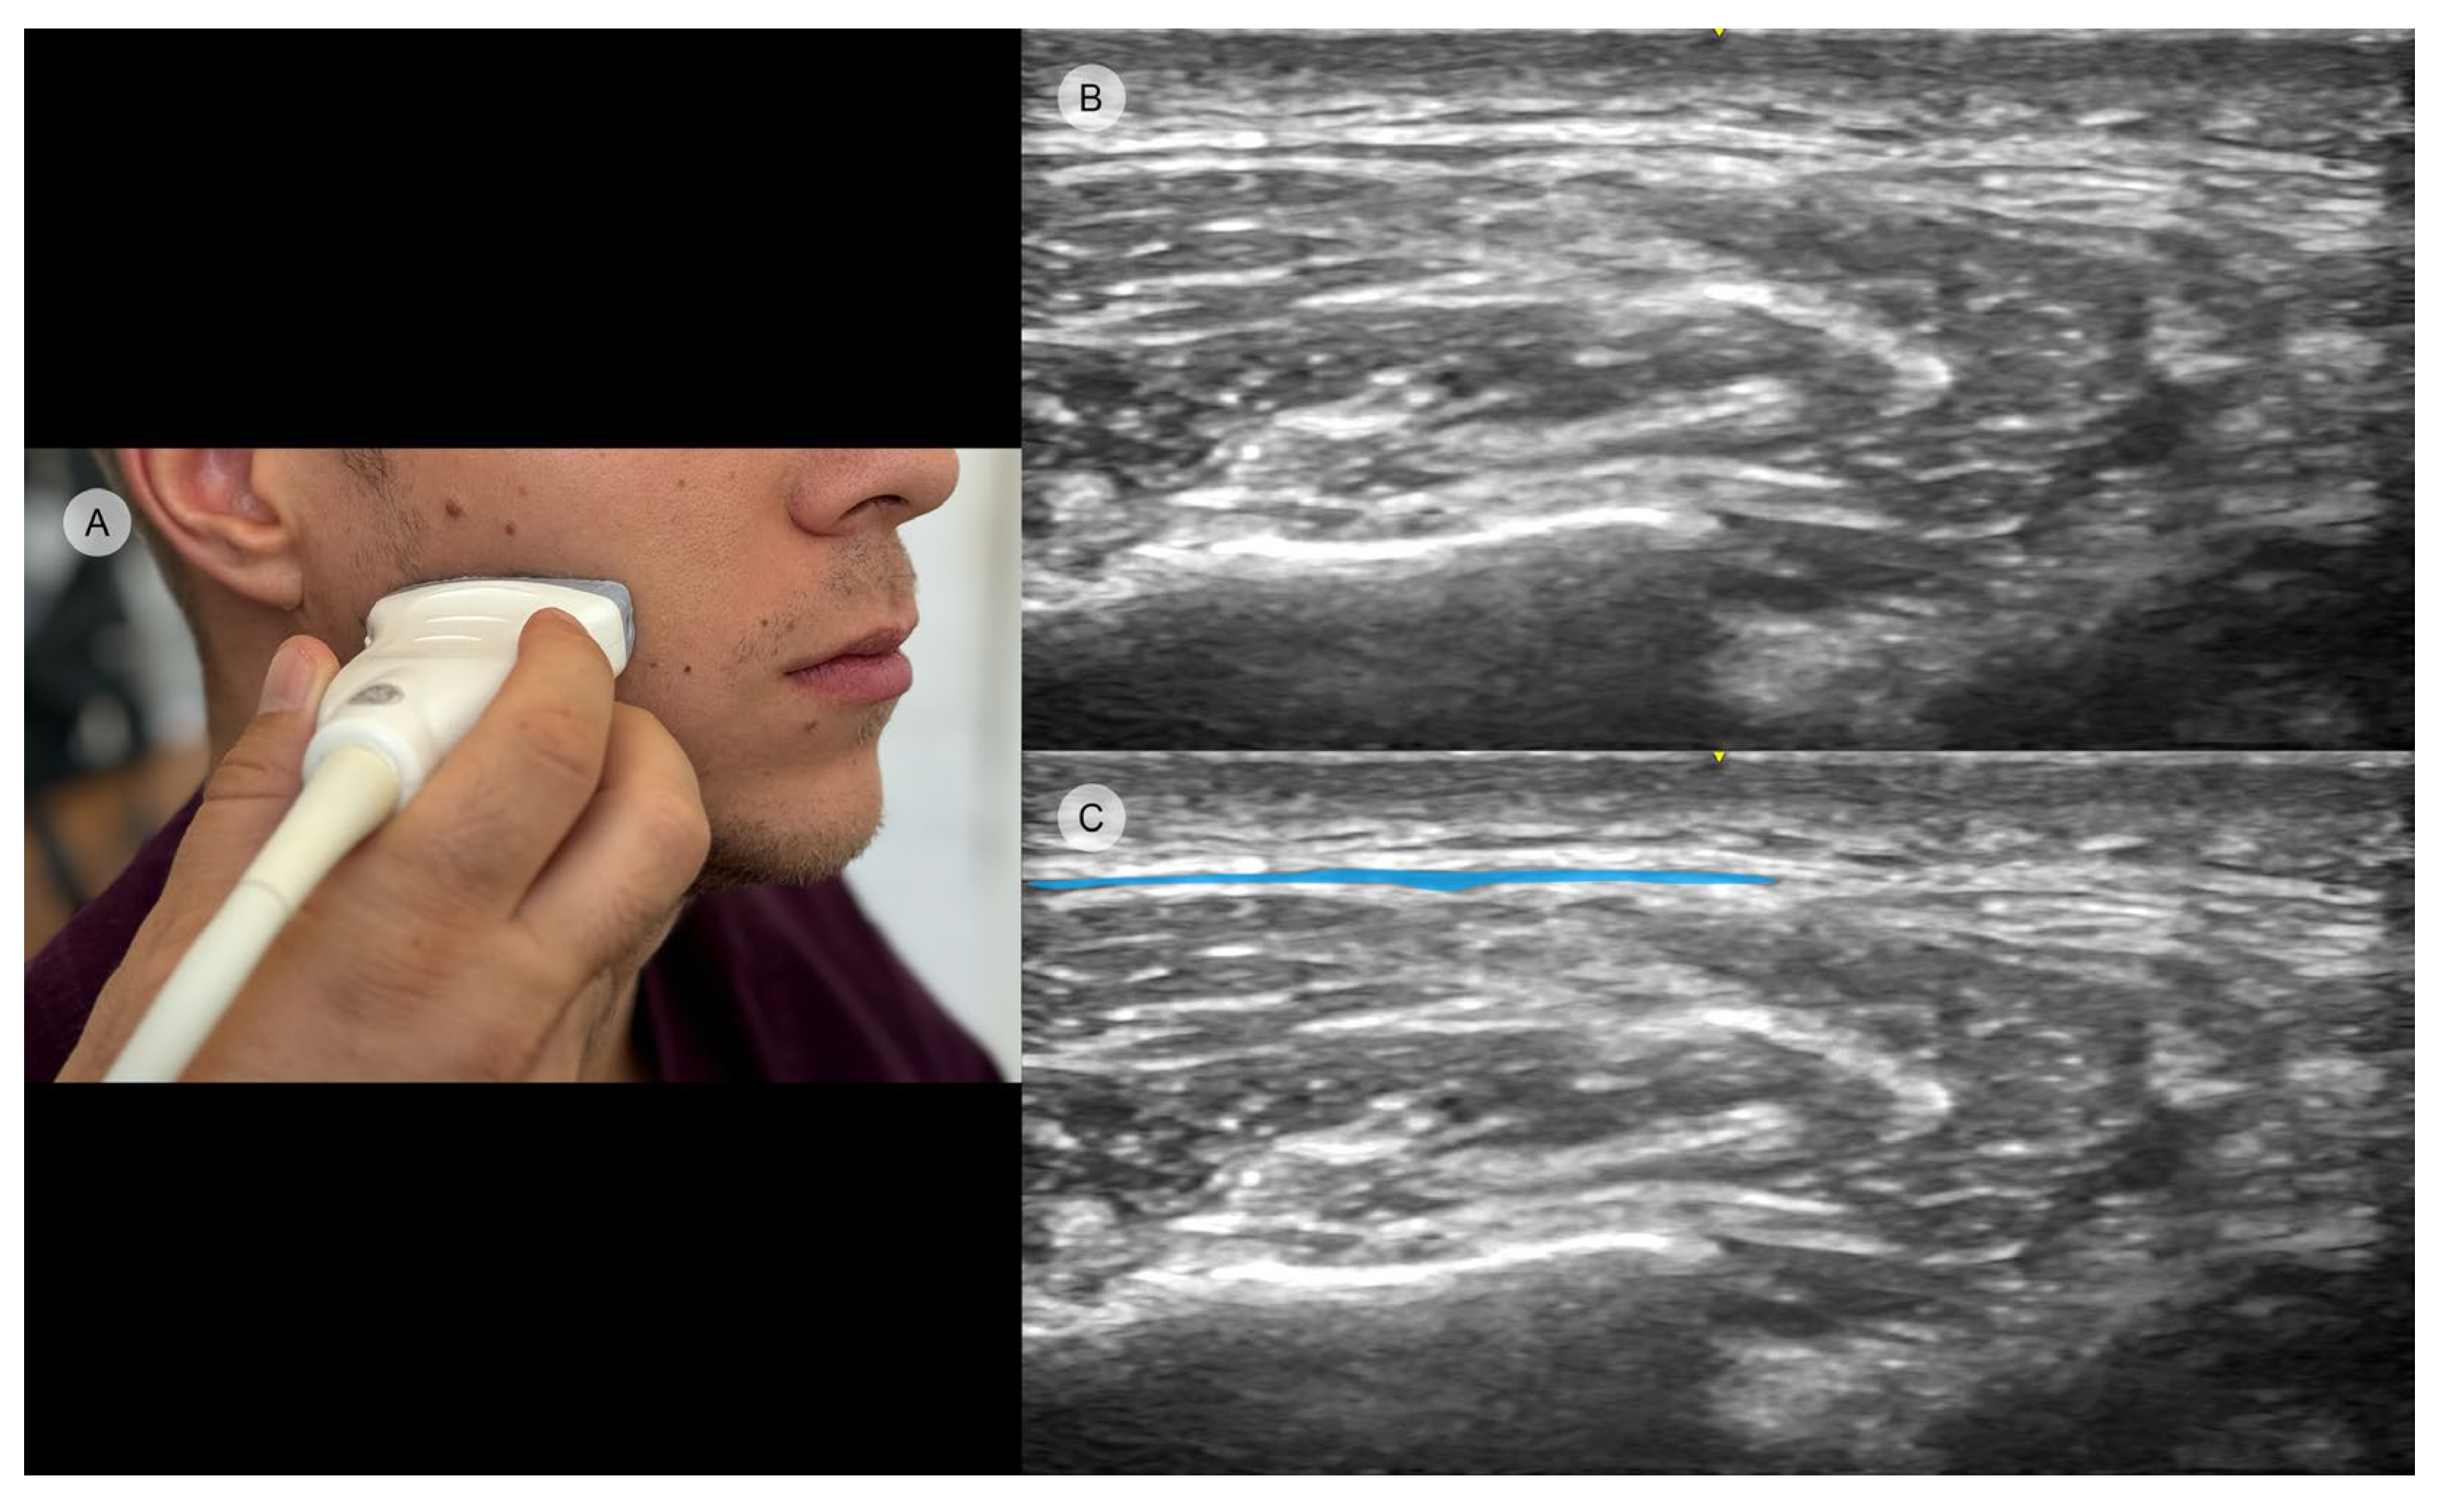

3. Anatomical Landmarks and Injection Techniques

4. Ultrasound as a Guidance Method to Enhance and Avoid Possible Complications